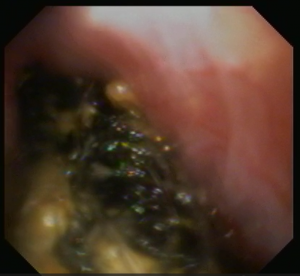

同じようにW字鉗子にて把持し引っ張ってこようとしましたが強固にはまっており摘出するのに少し時間を要しました。

摘出後は胃内に何も残っていいないことを確認し終了としました。